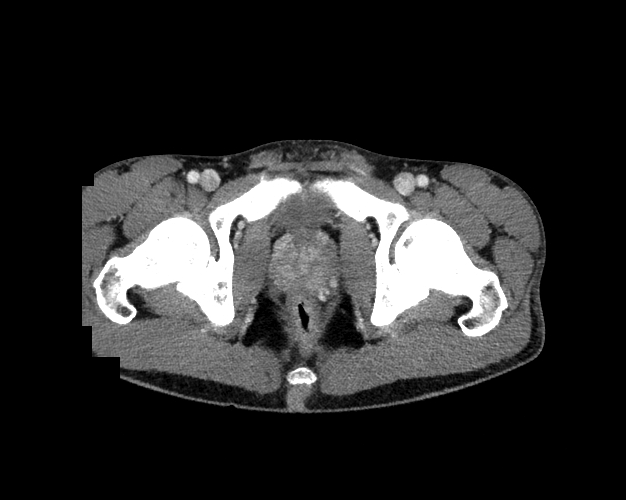

Pelvis

Covers pelvic MRI anatomy.